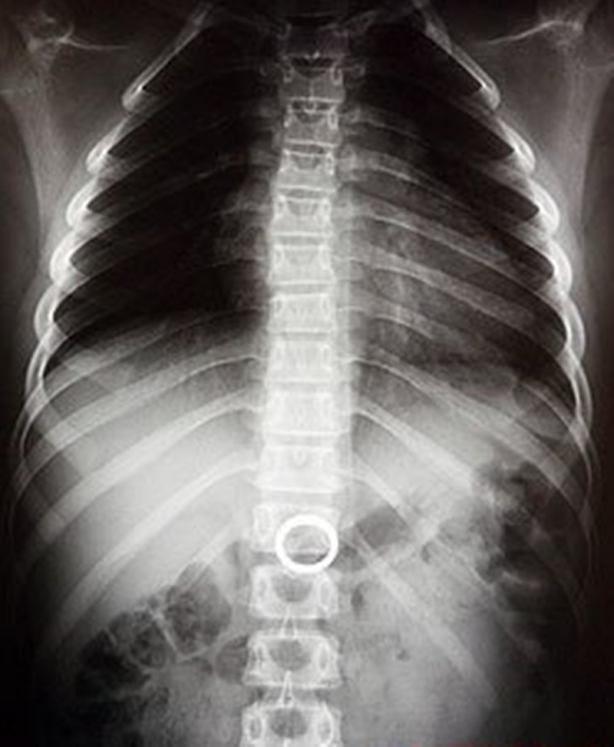

Annesinin evlilik yüzüğünü yutan ufak kız çocuğunun röntgen filmi.